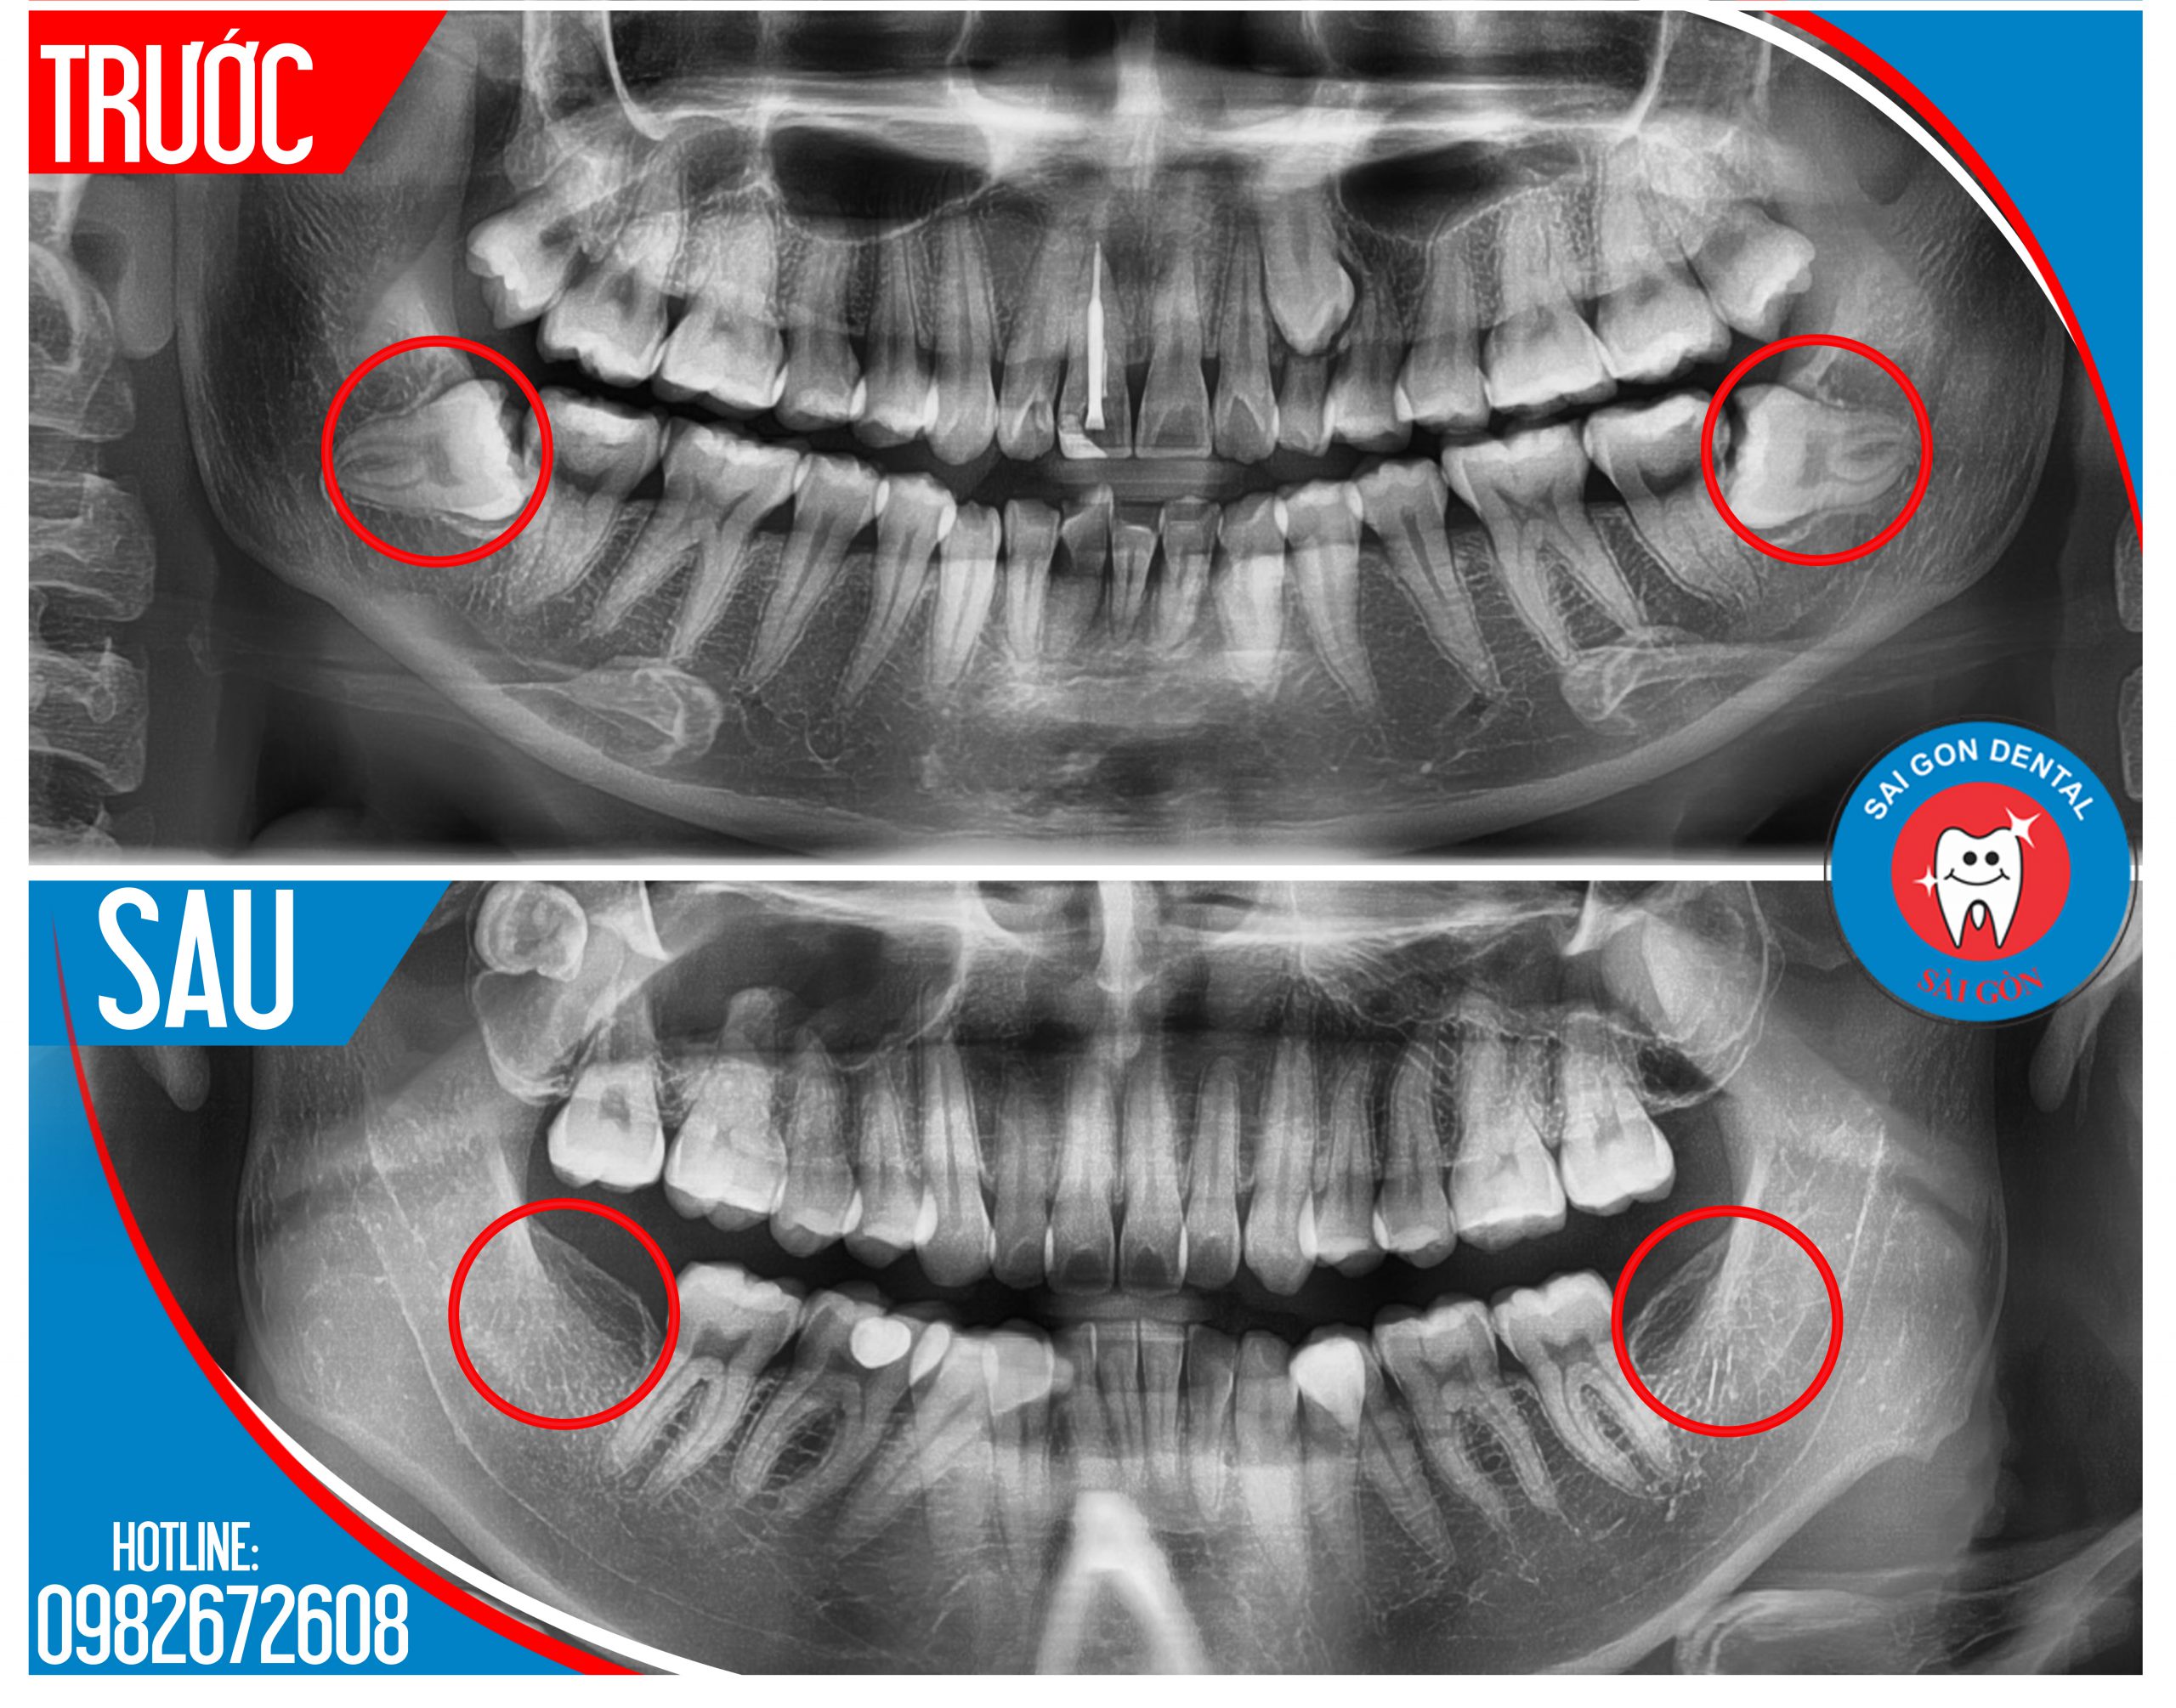

- Chụp phim X-Quang quanh chóp Kỹ thuật số: Nhằm mục đích lựa chọn phương pháp tiểu phẫu thích hợp nhất, qua phim chụp sẽ xác định được hình dáng và số lượng chân răng, hướng răng và góc độ lệch, độ sâu của răng số 7 đã đến tủy hay chưa.